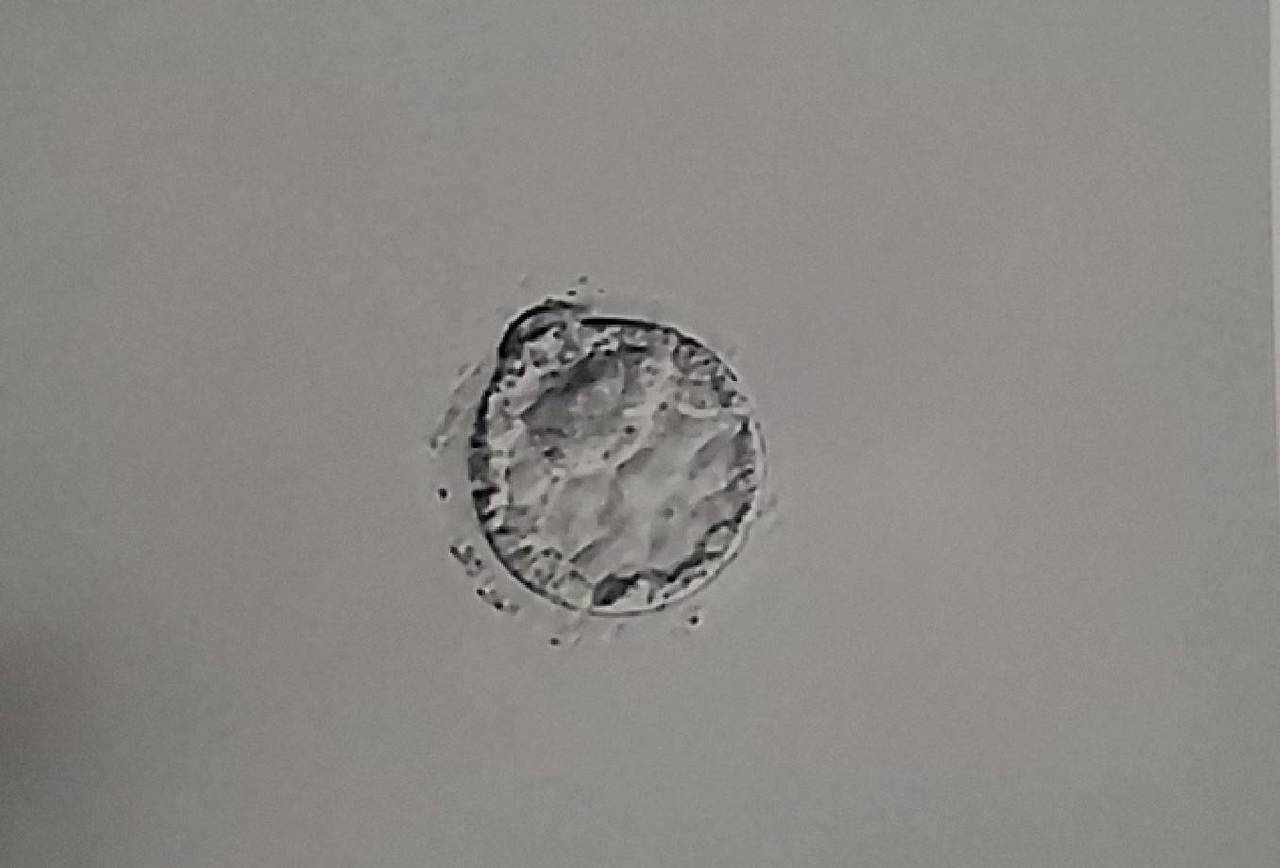

卵子の成熟不全(見た目は正常でも中身が未熟)

採卵時に「成熟卵」と判断されても、

があると、受精がうまく進まないことがあります。

これは顕微鏡では見えない質の問題です。

• 染色体のエネルギー不足

• ミトコンドリア機能の低下